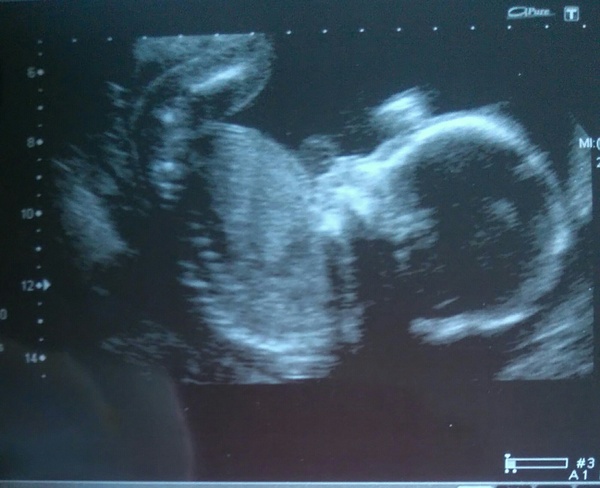

Annabrooke90 · 21/04/2016 19:09

Attached one of the pictures where she is really curled up haha.

What a lovely and clear pic, Annabrook!